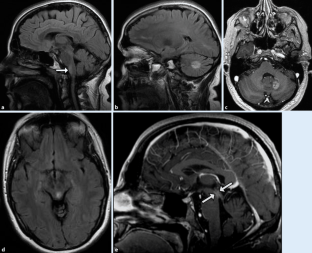

Abb. 3